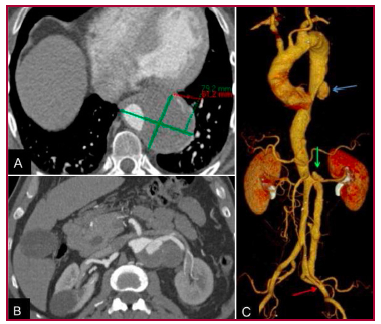

En el examen físico pudo constatarse un latido aórtico expansivo y pulsos femorales y poplíteos presentes. La angiotomografía realizada evidenció una gran úlcera en la aorta torácica descendente asociada a un hematoma intramural, con un diámetro transverso aórtico de 79 mm (Fig. 1A) y una disección crónica con LF permeable y dilatación aneurismática en la aorta abdominal; en este sector, el diámetro transverso alcanzó 59 mm (Fig. 1B). También se pudo observar el nacimiento del tronco celíaco (TC), la arteria mesentérica superior (AMS) y la arteria renal derecha del LV y la arteria renal izquierda originada del LF, con una reentrada en este sector. En la aorta abdominal infrarrenal se observó compresión del LV y en la arteria ilíaca externa izquierda una reentrada distal (Fig. 1C).